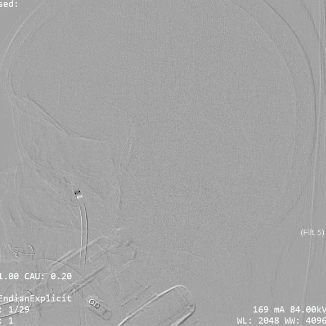

透视下可见Syphonet®取栓支架通体显影,有利于观察支架形态。